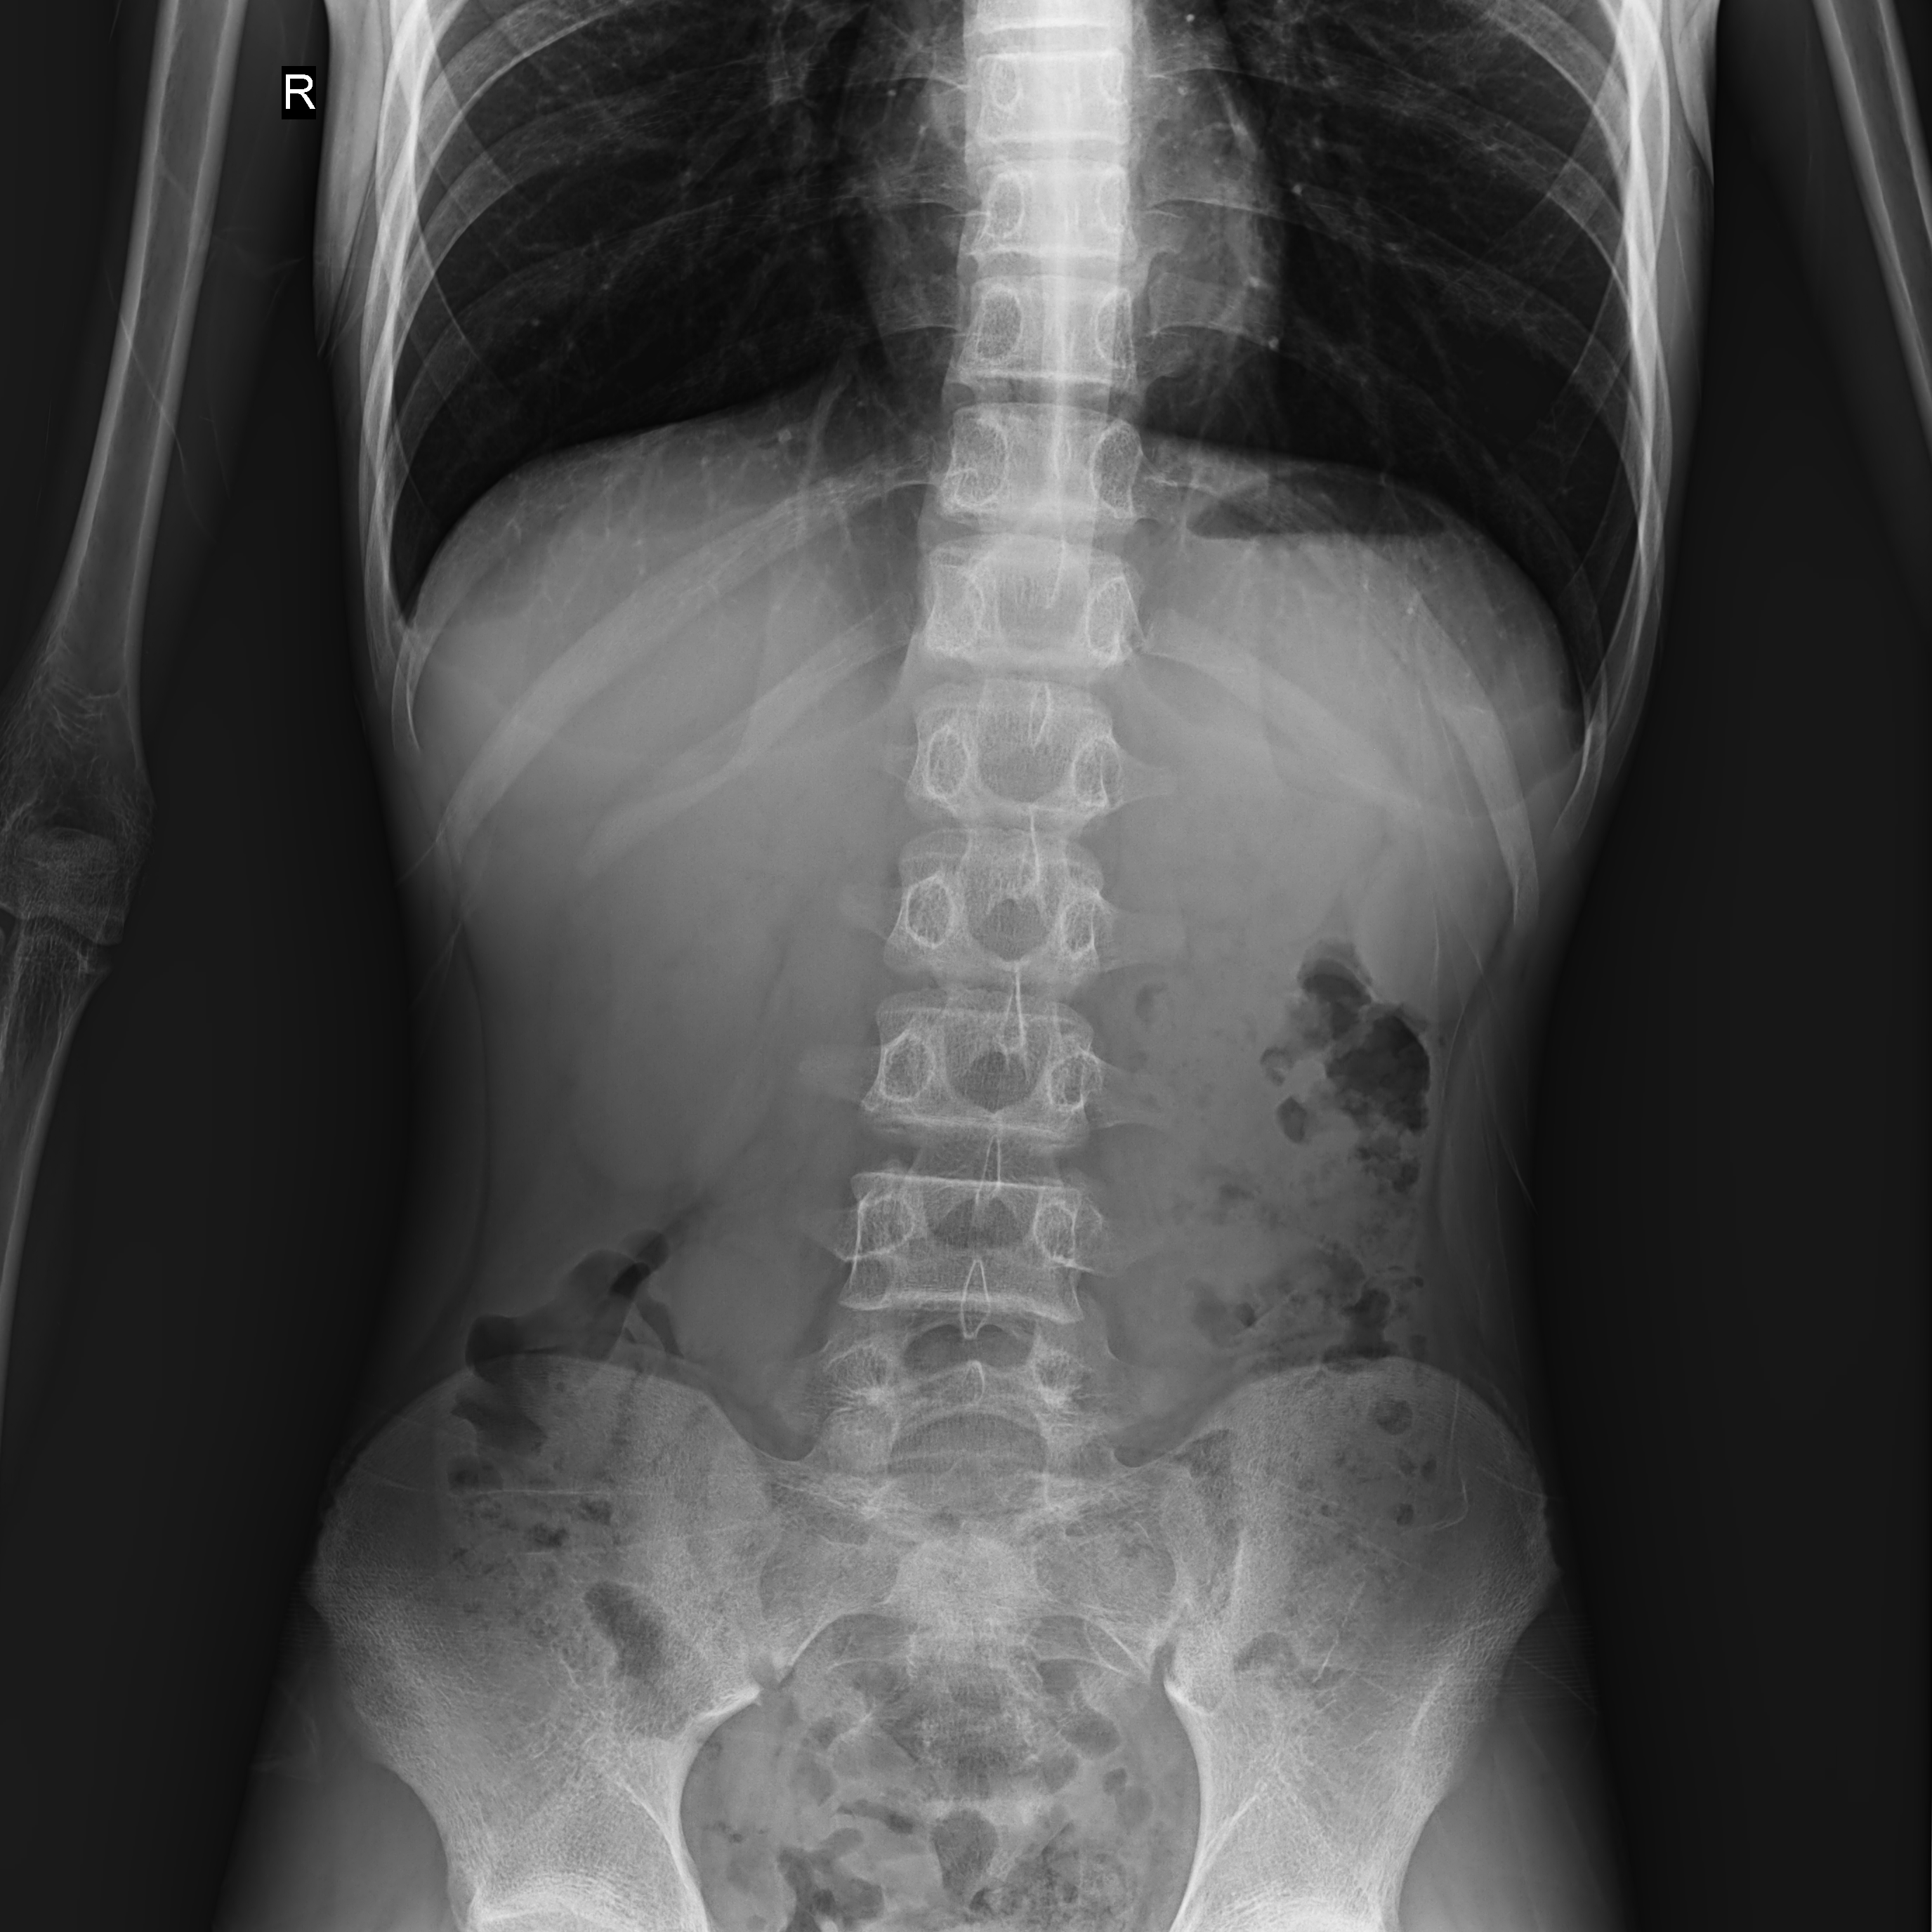

球管傾斜攝影角度-45°~45°,滿足臨床各部位各角度的攝影需求。如:髕骨軸位、頸椎正位、骶尾椎、鼻竇瓦氏位、梅氏位等部位檢查。

點片裝置移動范圍大,無需患者移動就能完成全身各部位的檢查;

床面橫向移動,輕松實現(xiàn)機動人不動。